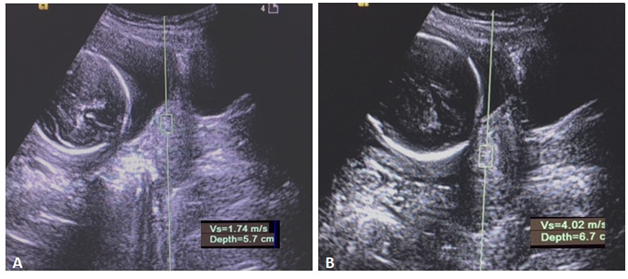

PTB prediction is important for both the clinician’s and the patient’s perspective as it can lead to planned management of such cases and reduces the neonatal morbidity. There is 50% increased risk of PTB in a woman who has experienced two or more prior PTBs.6 Clinical evaluation of the cervix is usually done by finger palpation method which measures the length from the level of external os to the cervico-vaginal junction giving the Bishop’s scoring. The cervical isthmus portion could not be assessed; which leads to the underestimation of the length by nearly 12mm compared to the USG in about 80% cases during the second and third trimester.7 Here we will discuss the routine USG assessment of the cervix with role of cervical elastography and fetal adrenal gland biometry in prediction of the preterm birth (Figure 1).

Figure 1 Transabdominal Ultrasound of the cervix. (A) Cervical Length measurement. (B) Funnelling of the cervix (white arrow) and amniotic fluid debris near internal os (asterisk*).

Multicentric study by Iams et al.,10 proposed the concept of ‘short cervix’ on USG as less than 25mm (or <10th centile length at 24-28weeks). The earlier in gestation, the shorter the cervix, the greater is the risk of PTB. Rate of cervical change or progressive shortening of the cervix is more important than a single measurement, hence a term ‘short and shortening’ or ‘short but stable’ cervix is described. There are other morphological features like cervical canal dilatation, funneling, sludge or debris in the amniotic fluid which can be combined in support to predict the preterm delivery (Figure 2).